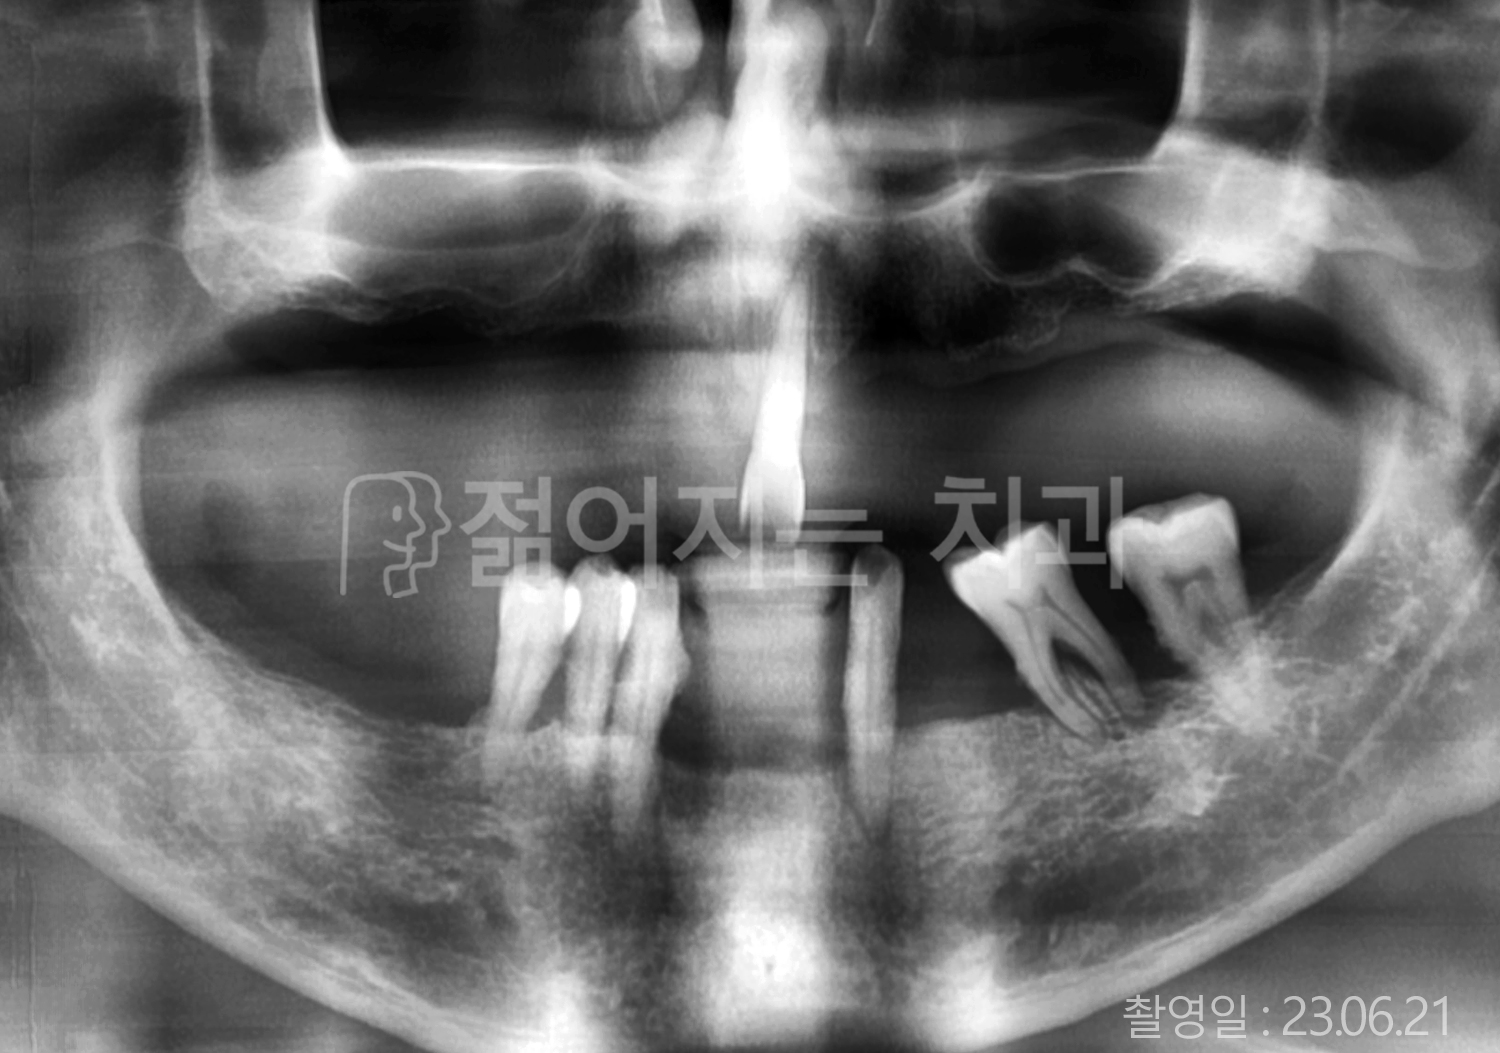

• 70대 고혈압, 당뇨 전체치아 10개 이상 임플란트

• 50대 고혈압, 당뇨 전체치아 10개 이상 임플란트

• 60대 고혈압, 당뇨 전체치아 10개 이상 임플란트

• 50대 전체치아 10개 이상 임플란트

• 70대 당뇨 전체치아 10개 이상 임플란트

• 80대 전체치아 10개 이상 임플란트

• 40대 전체치아 10개 이상 임플란트

• 60대 고협압, 고지혈증 전체치아 10개 이상 임플란트

• 60대 전체치아 10개 이상 임플란트